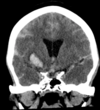

Which of the following mechanism of TBI is depicted in the CT?

1- Skull fracture

2- Contusion (bruise)

3- hematomas (blood clots)

4- lacerations (tear)

5- Diffuse axonal injury (nerve damage)

A